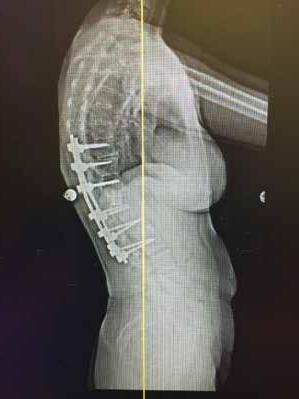

Total disc replacement (TDR) may be an alternative to spinal fusion for patients with cervical or lumbar herniated discs or degenerative disc disease.

The goals of total disc replacement surgery are to maintain segmental spinal motion, relieve pain, increase activity, restore disc height and proper spine curvature, and reduce post-operative recuperation time.

If you are experiencing neck or back pain and are considering surgery, isn't it worth your time to schedule an appointment with Dr. Jason E. Garber to nd out if motion preservation technology is an option for you?

Dr. Garber is one of Southern Nevada's most experienced spinal surgeons and a leader in arti cial disc replacement surgery.